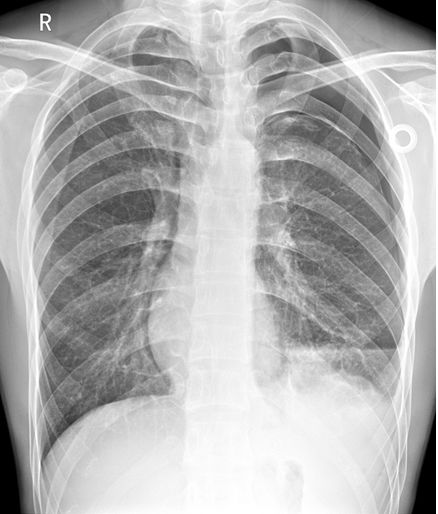

右上肺野见异常透亮无肺纹理区,内缘可见发线状肺组织压缩边缘,肺叶被压缩约30%(蓝色箭头)。心影及纵隔向对侧轻度移位(蓝色直线)。两膈面光滑,肋膈角锐利。